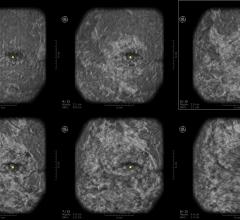

May 24, 2022 — A special type of MRI found lung abnormalities in patients who had previously had COVID-19, even those ...